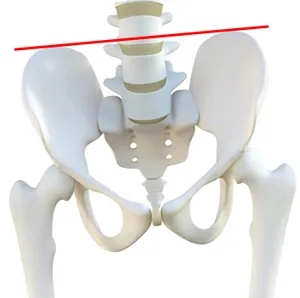

骨盤は、「 仙骨」・「 寛骨」・「 尾骨」という3つの骨によってできています。

この3つの骨がバランスを取り合って骨盤という骨を形成しています。

この3つの骨が、前後左右に傾いたり、ずれてしまったり、ねじれてしまうことで「骨盤のゆがみ」になります。

骨盤を構成する骨「仙骨」「寛骨」「尾骨」